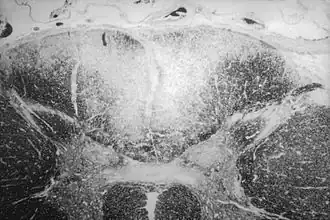

| Secção axial da medula espinhal mostrando a destruição causada pela sífilis (área esbranquiçada, no região central superior) das colunas posteriores, que carregam informação sensorial do corpo em direção ao cérebro | |

Tabes dorsal é uma lenta degeneração de neurônios que carregam informação sensorial para o cérebro. Os nervos que se degeneram nesta doença estão localizados nas colunas dorsais da medula espinhal e carregam informações que ajudam a pessoa a manter seu senso de posição (propriocepção), senso de vibração e toque fino (sensibilidade epicrítica).